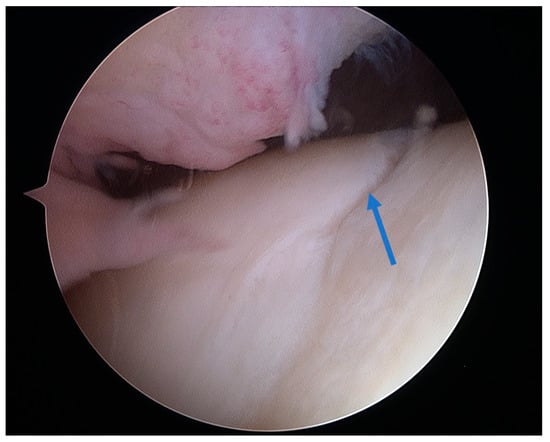

Figure 4.

Arthroscopic view of grade II lesion on the femoral trochlear groove with visible longitudinal fissures (arrow).